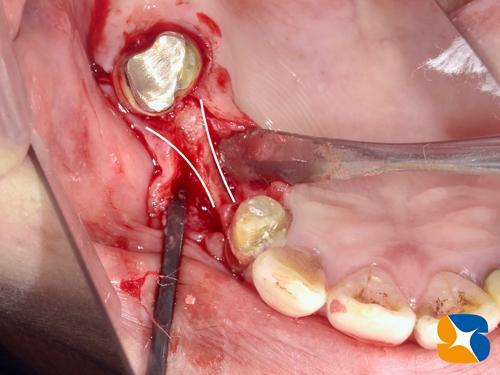

抜歯した奥歯の根が、著しく溶けて短くなっています。

これを目にした瞬間、今までの経験上とても嫌な予感がしました。

抜いた歯の根の周りは、かなり大きく骨が欠落していました。

CTを用いて入念にチェックしていましたが、これは想定外でした。

水色の2箇所の予定場所(=写真=)の中間位置に太めにインプラントを移植することにしました。